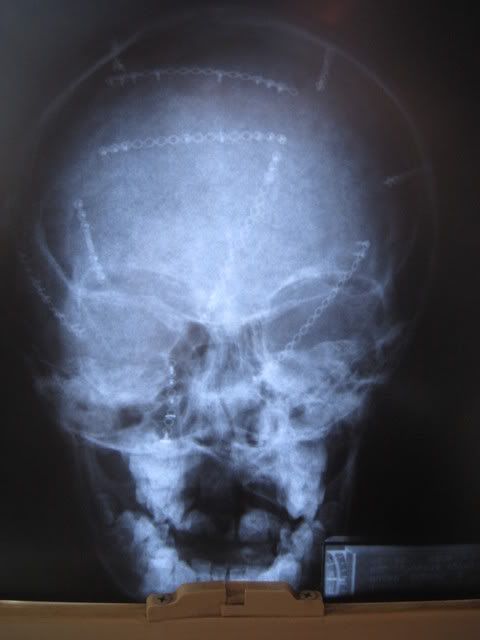

Here's the xrays. These were taken when he was 9 years old so the bone has grown over many of the 'plates' and screws.

ETA: I'm not sure if this is the right way to link to the picture I want to share...BEFORE YOU LOOK READ THIS WARNING: This is a bloody picture of the inside of Robert's skull taken during surgery to show the placement of the screws and plates: -- OK If you're ready click here